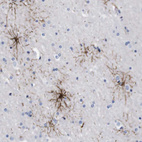

Immunohistochemical staining of human cerebral cortex shows strong cytoplasmic positivity in glial cells.